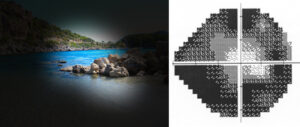

“Il glaucoma – spiega Stefano Miglior, direttore della clinica oculistica Policlinico di Monza, Università Milano Bicocca, nonché Presidente dell’Associazione italiana Studio Glaucoma, è una patologia degenerativa e se non viene monitorata e controllata con la terapia farmacologica o chirurgica porta alla cecità irreversibile. Coinvolge in genere, entrambi gli occhi determinando danni permanenti al nervo ottico. (oggi è la seconda causa di cecità nei Paesi industrializzati).Il fattore di rischio più importante è la pressione oculare elevata, ma in un terzo dei casi viene osservato in pazienti con pressione oculare normale. Il soggetto può andare incontro a una progressiva riduzione del campo visivo fino alla visione cosiddetta “tubulare” che dà l’impressione di guardare attraverso un cono, perché si riesce a vedere solo una piccola parte di ciò che si ha davanti. Non esiste una cura definitiva, ma la patologia può solo essere rallentata. E’ stato osservato che in alcuni pazienti glaucomatosi si assisterebbe anche a una progressiva compromissione strutturale e funzionale di zone cerebrali non propriamente deputate alla visione. Non è raro che le persone non si accorgano, anche per lungo tempo, di esserne affette e arrivino dall’oculista quando la situazione è ormai già compromessa. I controlli oculistici periodici sono fondamentali.”

Il Glaucoma colpisce di solito oltre i 60 anni ma può insorgere anche tra i più giovani. “A tutt’oggi – sottolinea l’esperto- non ci sono nuove armi nella terapia medica del glaucoma ma abbiamo a disposizione una significativa batteria di molecole che, in mono-terapia o terapia combinata, permettono di gestire un numero elevato di pazienti. “Le metodiche diagnostiche del glaucoma non sono invasive e si basano su tre fattori riferisce Stefano Miglior:“disponibilità dell’individuo sano a sottoporsi a visite oculistiche di controllo ripetute nel tempo (se l’individuo è a conoscenza di parenti stretti affetti da glaucoma, farebbe bene a cominciare a farsi visitare già in età giovanile); esperienza del clinico oculista che visita il presunto paziente e corretta interpretazione dei risultati degli esami di riferimento in rapporto ai dati clinici osservati sul presunto paziente.